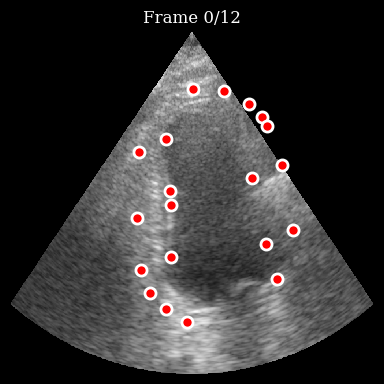

Visualize the initial points

[7]:

fig, ax = plt.subplots(figsize=(4, 4))

ax.imshow(frames[0], cmap="gray", aspect="auto")

ax.plot(

initial_points[:, 1],

initial_points[:, 0],

"ro",

markersize=8,

markeredgecolor="white",

markeredgewidth=2,

)

ax.set_title("Initial Tracking Points")

ax.axis("off")

plt.tight_layout()

plt.show()

../../_images/notebooks_models_speckle_tracking_example_12_0.png